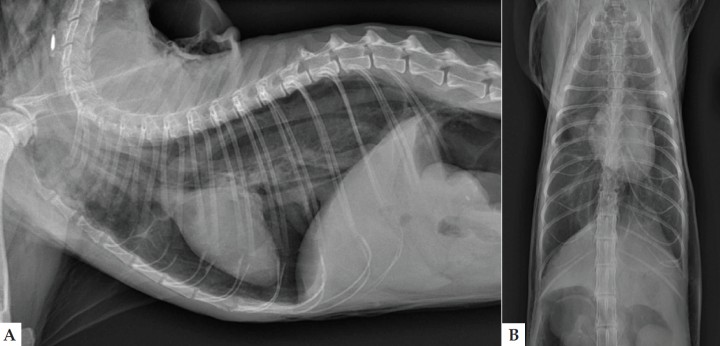

El análisis de sangre no reveló anomalías significativas. Se realizaron radiografías lateral derecha y ventrodorsal de la cavidad torácica (Fig. 1).

<p>Radiografías de tórax en proyección lateral derecha (A) y ventrodorsal (B) en un gato Persa de 15 años con un cuadro de disnea y enfisema subcutáneo.</p>

Figura 1

Radiografías de tórax en proyección lateral derecha (A) y ventrodorsal (B) en un gato Persa de 15 años con un cuadro de disnea y enfisema subcutáneo.

En la proyección lateral derecha del tórax (Fig. 2A) se observa una mejor visualización de las estructuras mediastínicas craneales, incluyendo la pared traqueal, el esófago y los vasos sanguíneos, al aparecer rodeadas por gas. Los hallazgos son sugerentes de neumomediastino. También se observa desplazamiento dorsal de la silueta cardiaca por una banda de opacidad gas y retracción del lóbulo pulmonar caudal, compatible con neumotórax. Hay aumento de la densidad radiológica del pulmón, posiblemente por atelectasia pulmonar secundaria.

<p>Mismas imágenes que en Figura 1. Proyección lateral de tórax (A): Neumomediastino (elipse); neumotórax (asterisco blanco) con retracción del lóbulo pulmonar caudal (cabeza de flechas blancas); enfisema subcutáneo (flechas blancas) y neumoretroperitoneo (doble asterisco blanco). Osteofitos o artrolitos a nivel de las articulaciones escapulohumerales y pequeñas mineralizaciones a nivel de las siluetas renales (flecha negra). En la proyección ventrodorsal (B) realizada tras drenaje del neumotórax se observa mayor distensión pulmonar.</p>

Figura 2

Mismas imágenes que en Figura 1. Proyección lateral de tórax (A): Neumomediastino (elipse); neumotórax (asterisco blanco) con retracción del lóbulo pulmonar caudal (cabeza de flechas blancas); enfisema subcutáneo (flechas blancas) y neumoretroperitoneo (doble asterisco blanco). Osteofitos o artrolitos a nivel de las articulaciones escapulohumerales y pequeñas mineralizaciones a nivel de las siluetas renales (flecha negra). En la proyección ventrodorsal (B) realizada tras drenaje del neumotórax se observa mayor distensión pulmonar.

Se aprecia gas en la región del cuello que se extiende a lo largo de la pared torácica y abdominal, compatible con enfisema subcutáneo, así como en área retroperitoneal craneal, indicativo de neumoretroperitoneo. Como hallazgos incidentales se visualizan osteofitos o artrolitos a nivel de las articulaciones escapulohumerales, compatible con osteoartrosis, y pequeñas mineralizaciones a nivel de las siluetas renales.

Tras el drenaje del neumotórax se realiza la proyección ventrodorsal (Fig. 2B), ya que la disnea que presentaba el paciente previamente dificultaba realizar proyecciones adicionales. En la imagen se puede observar una mayor distensión pulmonar.